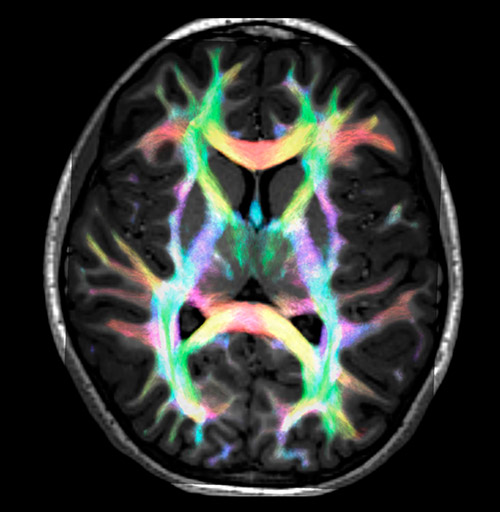

Fiber tracking based on CSD analysis of multishell DWI data and probabilistic tractography.

UVM research fiber tracking density

Fiber tracking from the left and right hippocampi to the fornix.

Fiber tracking from the left and right hippocampi to the fornix (green), and the corticospinal track based on a seed region of the posterior limb of the internal capsule.